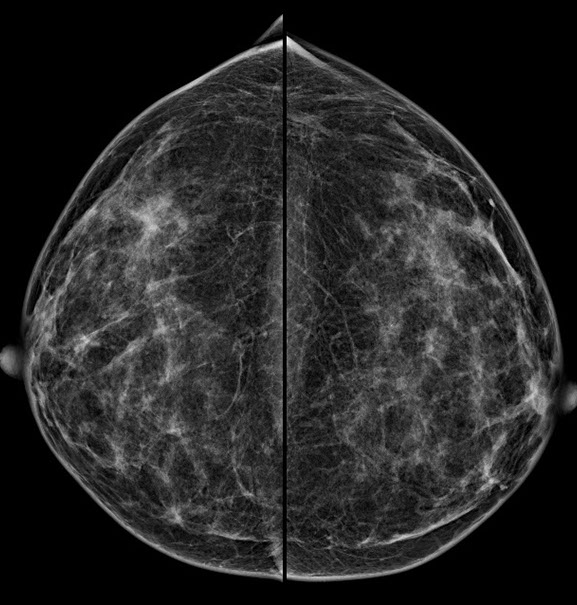

Bei der Mammographie handelt es sich um ein Röntgenverfahren, welches auf einem einfachen Prinzip beruht: Unterschiedliche Gewebestrukturen (Fettgewebe, Bindegewebe, Brustdrüsengewebe) haben eine unterschiedliche Dichte. Die bei der Mammographie verwendete weiche Strahlung wird von einzelnen Gewebekomponenten unterschiedlich absorbiert, woraus unterschiedliche Kontraste im Mammographiebild resultieren.

2.  Bessere Aussagekraft bei dichtem Brustdrüsengewebe

Vor allem junge Frauen bzw. Frauen vor der Menopause haben ein dichtes Brustdrüsengewebe. In der konventionellen Mammographie ließ sich dieses dichte Gewebe oft schlecht darstellen. Aufgrund von Fehlbelichtungen waren Wiederholungsaufnahmen notwendig, die eine zusätzliche Strahlenbelastung mit sich brachten. Die digitale Mammographie kann hingegen auch geringere Kontraste in sehr dichtem Brustdrüsengewebe deutlicher hervorheben und so eine zuverlässigere Diagnostik ermöglichen. Fehlbelichtungen wie bei der alten konventionellen Mammographie werden praktisch ausgeschlossen.

3.  Exaktere Bildanalyse – sicherere Diagnose

Durch die höhere Kontrastauflösung bei einem höheren Kontrast-Rausch-Verhältnis wird die Erkennungsrate von malignitätsverdächtigen Veränderungen deutlich verbessert. Der Radiologe kann auf hochauflösenden 5 MP-Monitoren die Dichte, Form und Kontur von Gewebearealen wesentlich exakter differenzieren und so gutartige von bösartigen Herdbefunden sicherer unterscheiden. Im Speziellen sind Mikroverkalkungen auch bei der dichten Brust besser zu analysieren.

Die Diagnosesicherheit und Möglichkeit einer Brustkrebsfrüherkennung durch die Mammographie, hängt von der Dichte des Brustdrüsengewebes ab. Einteilung der Dichtegrade wurde vom American College of Radiology (ACR) übernommen.

Bei einem Dichtegrad 3 sinkt die Sensivität der Mammographie deutlich, bei Dichtegrad 4 liegt sie unter 50 %. Durch gleichzeitigen Einsatz der Ultraschalluntersuchung wird die Sicherheit in der Diagnoseerstellung jedoch wieder auf

ca. 90 % angehoben.

40 % der Mammakarzinome weisen Mikroverkalkungen auf. Mikrokalzifikationen sind auch bei sehr dichtem Brustgewebe immer sichtbar. Eine Mammographie sollte daher ab dem 40. Lebensjahr die primäre Untersuchungsmethode sein.